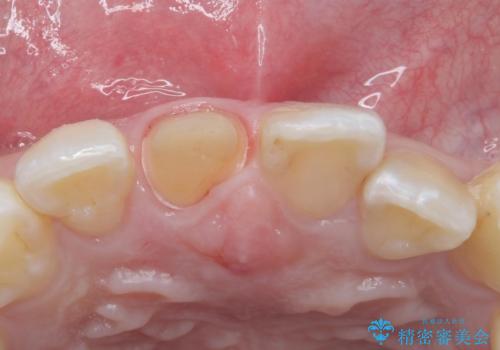

- 前歯のかぶせ物の色が気になるとのことで来院された患者様です。

セラミッククラウンで作り変えていきます。

- 右上1: 仮歯/11,000円、ジルコニアクラウン(スタンダード)/121,000円 合計132,000円(税込)費用は治療当時の料金となります